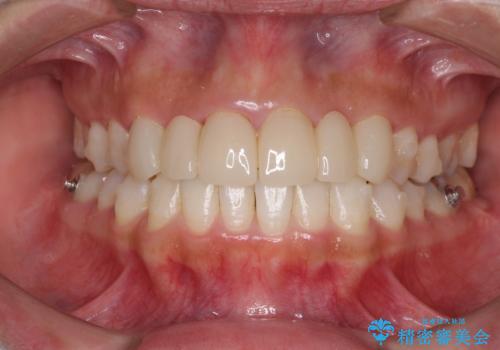

- 審美的ではない上の前歯とデコボコの下の前歯、歯茎が腫れている奥歯を気にして来院された患者様です。

根管治療の必要な歯がいくつかあるため、まずは根管治療を行い、その後インビザラインにて矯正治療を行うこととしました。

矯正治療後に前歯をセラミックブリッジに、奥の銀歯はセラミックインレーやPGAインレー(ゴールドインレー)にて補綴・修復治療を行うこととしました。

矯正治療により下顎前歯を整列させたため、上顎前歯のセラミックブリッジを補綴することで口元を少し下げることができました。

ヒトの目線がいつも口元に向けられているように感じることがなくなり、患者様には大変満足していただきました。